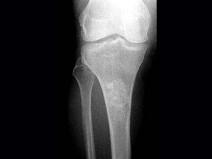

问题 女,年龄47岁,膝关节疼痛6月余,曾服用泼尼松(服用时间5个月),有骨性关节炎史,结合图像,最可能诊断是?(?)

选项 A.慢性化脓性骨髓炎 B.骨梗死 C.恶性骨肿瘤 D.内生软骨瘤 E.骨纤维结构不良

答案 B